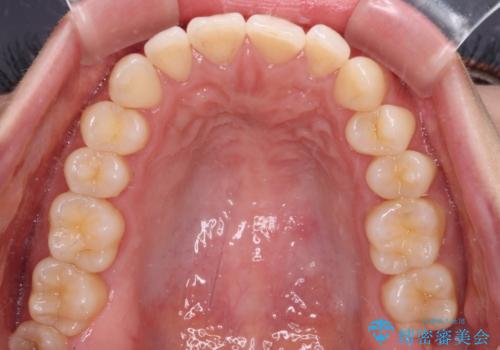

- 上下前歯の隙間と口元の出っ張った感じを気にして来院された患者様です。

上下の隙間は舌突出癖によるもので、またその癖により前歯が前方に出ている状態でした。

口元の出っ張りを改善するため、上下左右第一小臼歯4本を抜去し、ワイヤー装置にて矯正治療を行うこととしました。

舌の突出癖を改善するためのトレーニングをしっかりと行っていただいたことで、比較的スムーズに治療を進めることができました。

口元の突出感もしっかりと改善することができました。